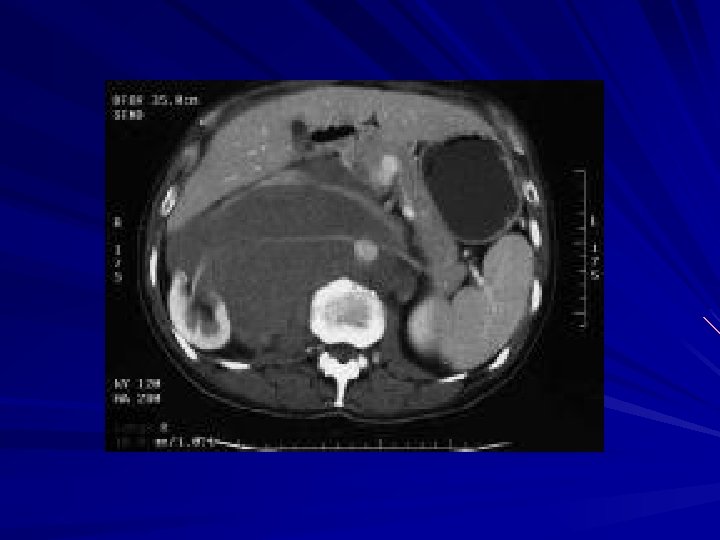

Protocol de investigatii I. Metode imagistice Urografia – Pentru stadializare – Evidentierea metastazelor ganglionare (indirect) Radiografia pulmonara – Metastaze pulmonare hematogene – Metastaze ganglionare mediastinale Tomografia Computerizata – Obligatorie pentru evidentierea metastazelor ganglionare limfatice Rezonanta Magnetica Nucleara – Aceleasi indicatii ca si TC

Urografie intravenoasa Suspiciune adenopatie periaortocava